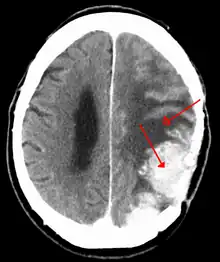

A contrast-enhanced CT scan of the brain, demonstrating the appearance of a meningioma

Meningiomata are visualized readily with contrast CT, MRI with gadolinium,[20] and arteriography, all attributed to the fact that meningiomata are extra-axial and vascularized. CSF protein levels are usually found to be elevated when lumbar puncture is used to obtain spinal fluid. On T1-weighted contrast-enhanced MRI, they may show a typical dural tail sign absent in some rare forms of meningiomas.[16]